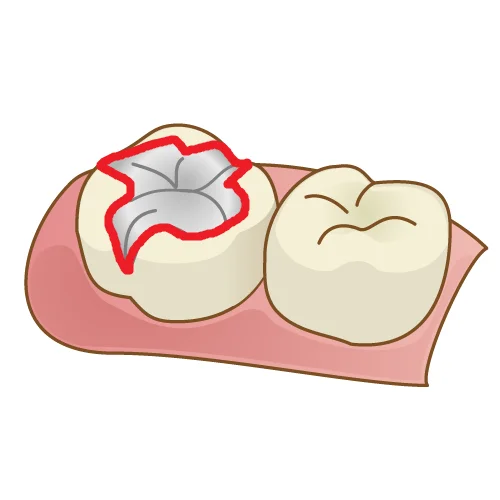

というのも・・・クラウンと違ってマージンラインの形が非常に複雑なためです。

※マージンというのは、歯と金属の境目の事です。そのマージンをつないだ部分をマージンラインと呼びます。(下図赤線の部分です)

クラウンの場合は、全周削るわけですから、マージンラインはほぼ楕円形になります。

金属やセラミックなどで修復物を作成するときに、このマージンラインが複雑であればあるほど適合を出すのが難しくなります。